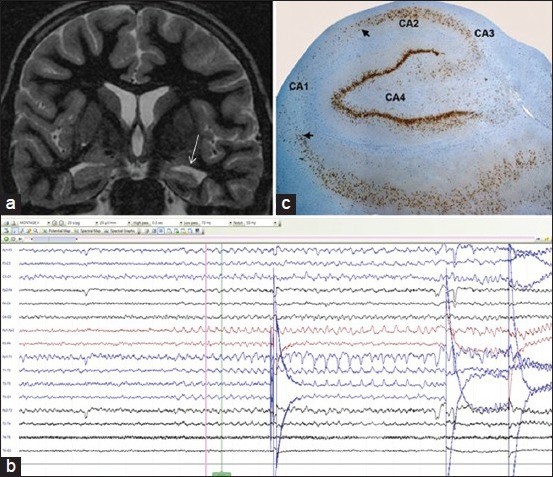

案例1:自2岁起,一名11岁女孩出现了复杂的部分性癫痫发作。尽管服用了多种抗惊厥药物,但她的癫痫发作频率仍为每月3-4次,临床检查未发现局灶性神经功能缺损。大脑的磁共振成像(MRI)显示【图a】,具有信号变化的左海马体积的损失和内部结构的丧失,而没有任何其他相关的病变。在视频脑电图(EEG)遥测过程中捕获的临床事件的特征是,右上肢肌张力障碍使患者向右转头。Ictal脑电图显示theta活性增强,左侧颞区出现尖锐波,在T5时相变【图b】。她接受了左颞叶开颅手术,左ATL以及杏仁核海马切除术。组织病理学揭示了CA1,CA3和CA4子区海马硬化的特征性神经元丢失,而CA1相对保留【图c】。在三个月的随访中,她仍然没有癫痫发作。

案例1:(图a)显示了垂直于海马体的高分辨率T2冠状图像,揭示了与内部结构的丧失有关的左海马体体积的损失。(图b)显示了theta活动的早期EEG积累,左侧颞叶区域出现尖锐波。(图c)显示Neu N染色上CA1,Ca3和CA4中神经元的丢失,提示中颞叶硬化(海马硬化)(NeunxObj.10),EEG=脑电图